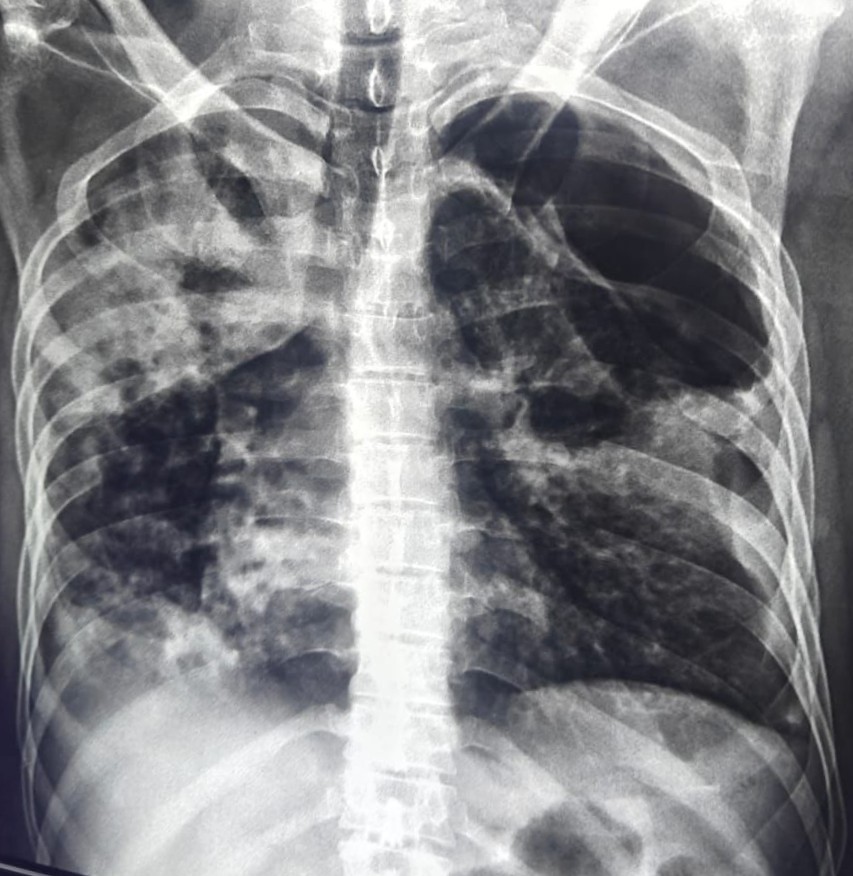

| 206 | IGGMC, Nagpur, Nagpur | P2 | 29-4266 | SHUBHAM URKUDE | Consent taken on Paper | 30 Yrs. |

Provisional Diag : PTB?

Final Diag : CLINICALLY DIAGNOSED PTB WITH OLD EPTB WITH LOSS TO FOLLOW UP IN CHRONIC ALCOHOLIC |

TB Case (Confirmed) | BILATERAL MIDDLE ZONE HAZZINESS/CONSOLIDATION | Abnormality visible on x-ray |

View |